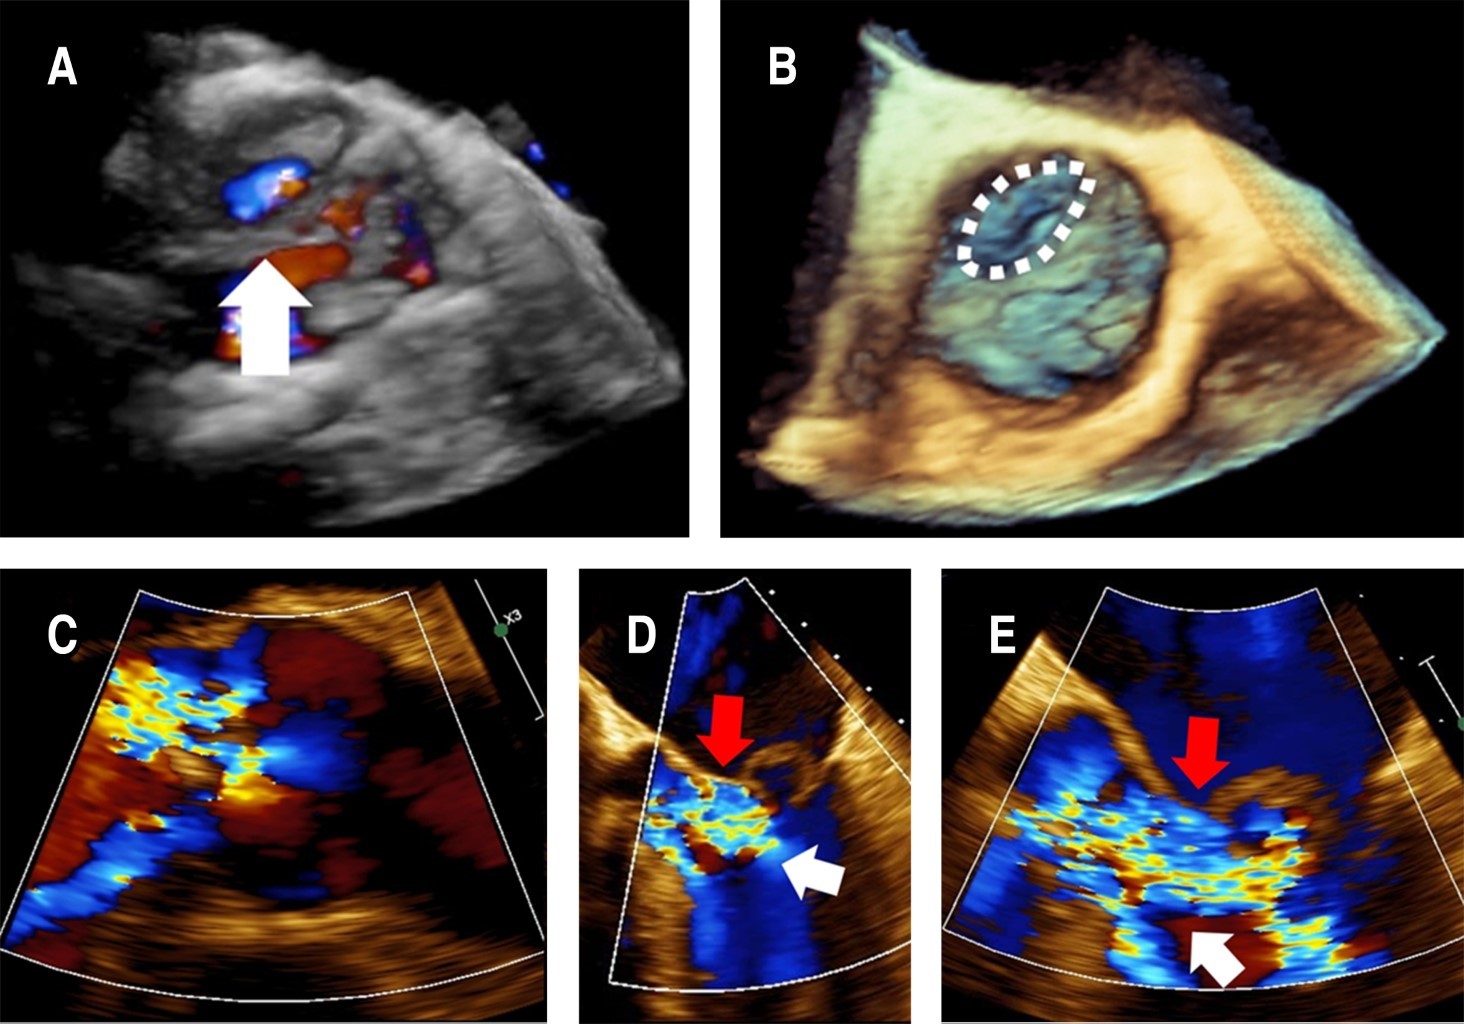

Based on the suspicion of IE, we obtained paired blood cultures and, subsequently, started vancomycin 1 g IV bid and ceftriaxone 1 g IV bid. A transesophageal echocardiogram (TEE) revealed an 11 × 5 mm vegetation on the P1 annulus of the mitral valve, a ruptured anterior mitral leaflet aneurysm resulting in severe mitral regurgitation accompanied by turbulent flow within the ruptured aneurysm (Figure 1) as well as a perforated non-coronary cusp of the aortic valve resulting in severe aortic regurgitation with regurgitation jet impinging on the anterior mitral leaflet (Figure 2). The blood cultures were positive for multi-sensitive Streptococcus gordonii, and antibiotics were deescalated to only ceftriaxone. Blood tests revealed a reduction in white blood cell count (8,400 mm3) and a decrease in inflammation markers (C-reactive protein 1 mg/dL, erythrocyte sedimentation rate 5 mm/h).

The echocardiographic appearance of MVA is characterized by a saccular bulge of the mitral leaflets that extends into the left atrium during systole and collapses during diastole.5,11 Other echocardiographic features vary from small saccular bulges, often challenging to identify due to vegetation, to large leaflet protrusions towards the left atrium, which may be associated with various degrees of mitral regurgitation and thrombosis.12 Among the differential diagnoses of MVA are mitral valve diverticulum, blood cysts of the papillary muscle, cardiac masses, chordal rupture, non-bacterial thrombotic endocarditis, mitral valve prolapse, flailing mitral leaflets, myxomatous degeneration, and infective vegetations. The color flow Doppler can support a correct diagnosis. A high-velocity regurgitant jet and direct communication between the aneurysm and the left ventricle support the diagnosis of a perforated aneurysm.3,5

Figure 2